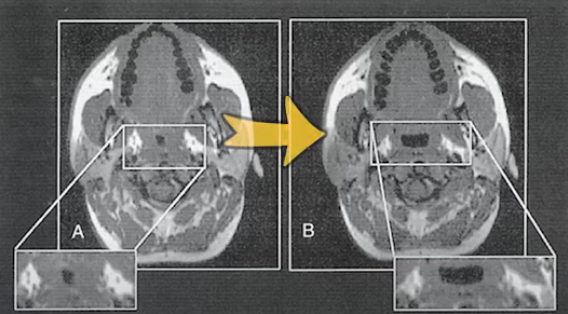

코골이에 가장 좋은건 체중감량이라고 말씀드렸습니다. 살이찌게되면 아래 그림과 같이 기도 주위의 지방질이 두꺼워지면서 기도를 좁게 만들어서 수면 무호흡증을 심하게 만듭니다.

그래서 살을 빼게되면 기도 주위의 좁아진 부분이 넓어지게 되니까, 숨쉬기가 편해져서 코골이나 수면무호흡이 줄어들게 됩니다.

또 한가지는 살이 빠지면 기도 주위만 빠지는 게 아니고 전체적으로 빠지게 됩니다. 전체적으로 내장지방 줄어들면서 폐의 공간이 넓어집니다. 누워있을 때를 생각해 보면 내장지방이 많으면 폐를 위로 올리게 됩니다. 그래서 기도를 밀리도록 만드니까 기도가 좁아지기 쉽게 만듭니다. 살이 빠지면 내장지방이 줄어들고 폐가 약간 밑으로 내려가면서 기도가 넓어질 수 있습니다.

그렇게 하지 않았을 때는 자고 나면 기도가 전체적으로 좁아지는 것이 관찰이 되었는데, 자기 한 시간 전에 30분 정도 하체 운동을 했을 때는 기도가 잘 유지가 되는 것을 확인했습니다.